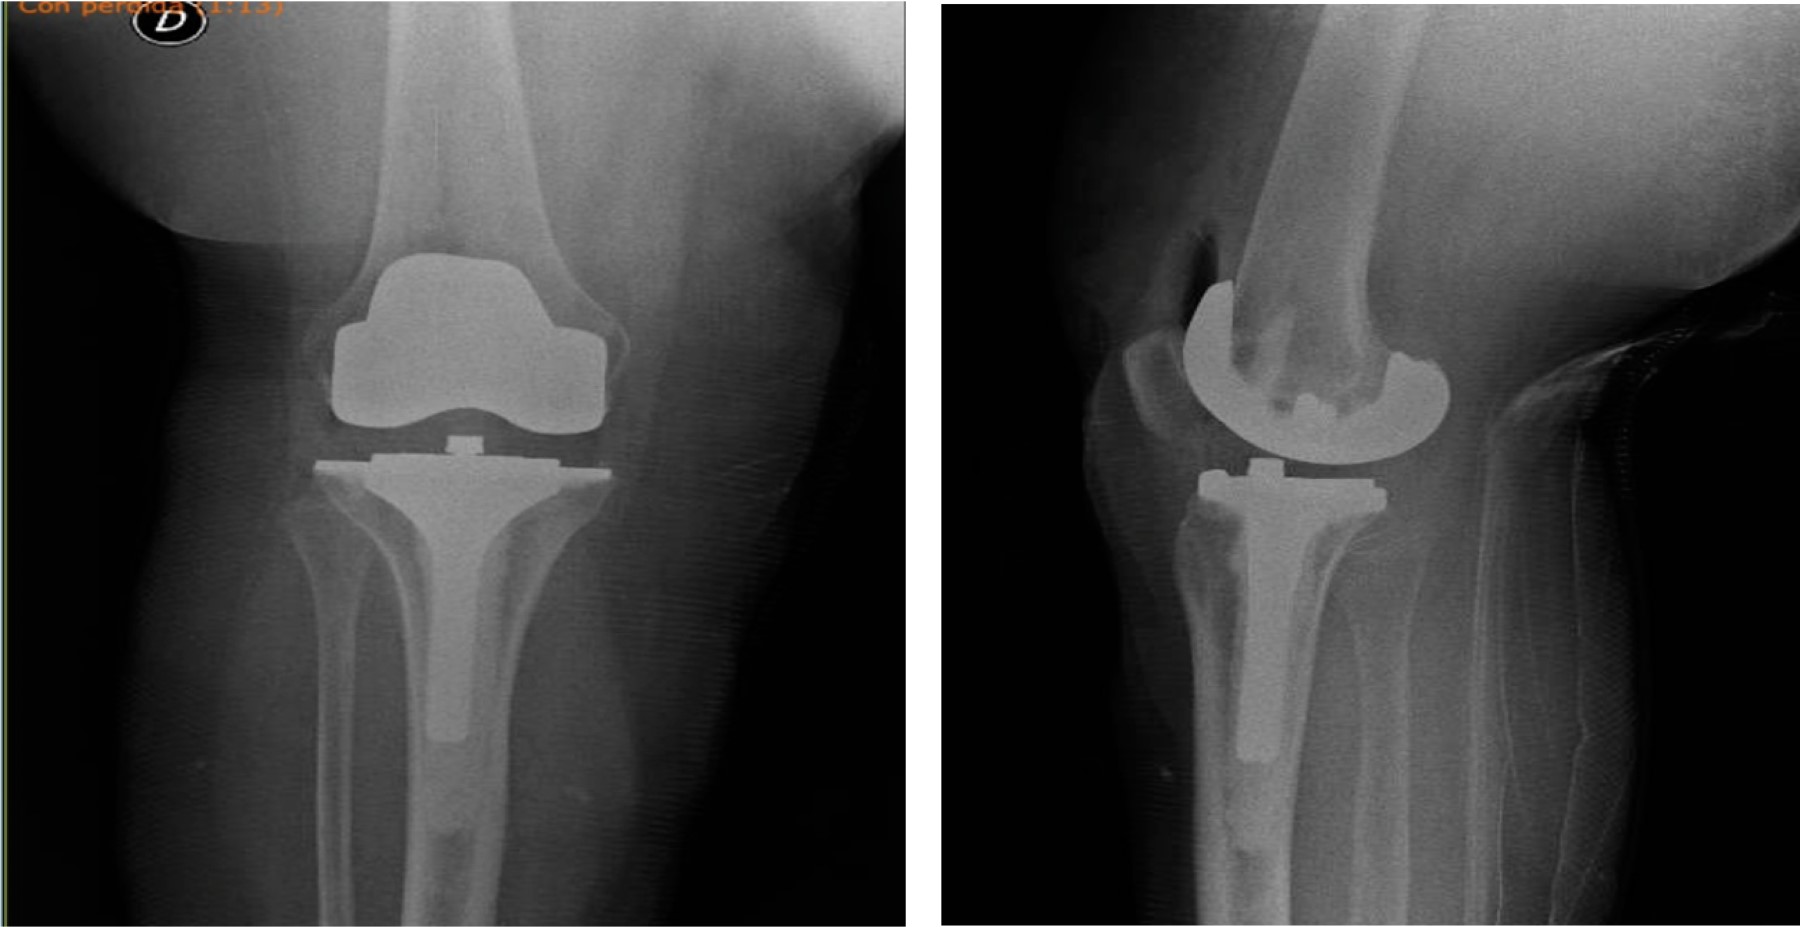

Figure 7

Figure 8